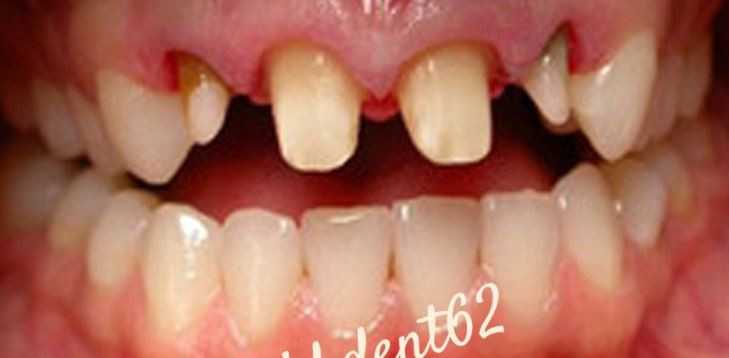

Установка мостовидного протеза

Пациент обратился с дефектами передних зубов верхней челюсти. Проведено лечение с установкой металлокерамических мостов

Установка керамической коронки

Пациент обратился в клинику с жалобой на сколы передних зубов верхней челюсти после травмы. Проведено удаление сломанных корней зубов и перелечивание оставшихся. Были установлены коронки, постоянные на каркасе из диоксида циркония, облицованные керамикой.